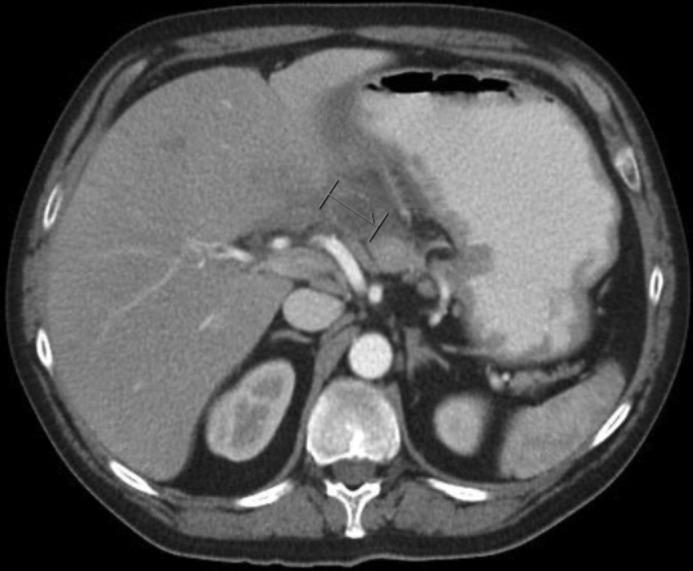

Ectopic pancreas is an uncommon finding in the stomach. Complications are rare but can lead to significant morbidity and even mortality. We report a 49-year-old man who presented with upper abdominal pain, vomiting, and weight loss and was found to have a gastric wall abscess that developed a few weeks after endoscopic biopsy of a gastric ulcer. After medical treatment failed to resolve his symptoms, he underwent distal gastrectomy with Roux-en-Y gastrojejunostomy. Postoperatively, the gastric wall abscess was determined to have derived from a focus of ectopic pancreatic tissue with evidence of ectopic chronic pancreatitis.

异位胰腺在胃中是一种罕见的发现。并发症很少见,但可导致严重的发病甚至死亡。我们报告一名49岁男性,他出现上腹部疼痛、呕吐和体重减轻,在内镜下对胃溃疡进行活检几周后发现胃壁脓肿。在药物治疗未能缓解其症状后,他接受了远端胃切除术及Roux-en-Y胃空肠吻合术。术后,确定胃壁脓肿源自异位胰腺组织灶,并伴有异位慢性胰腺炎的证据。